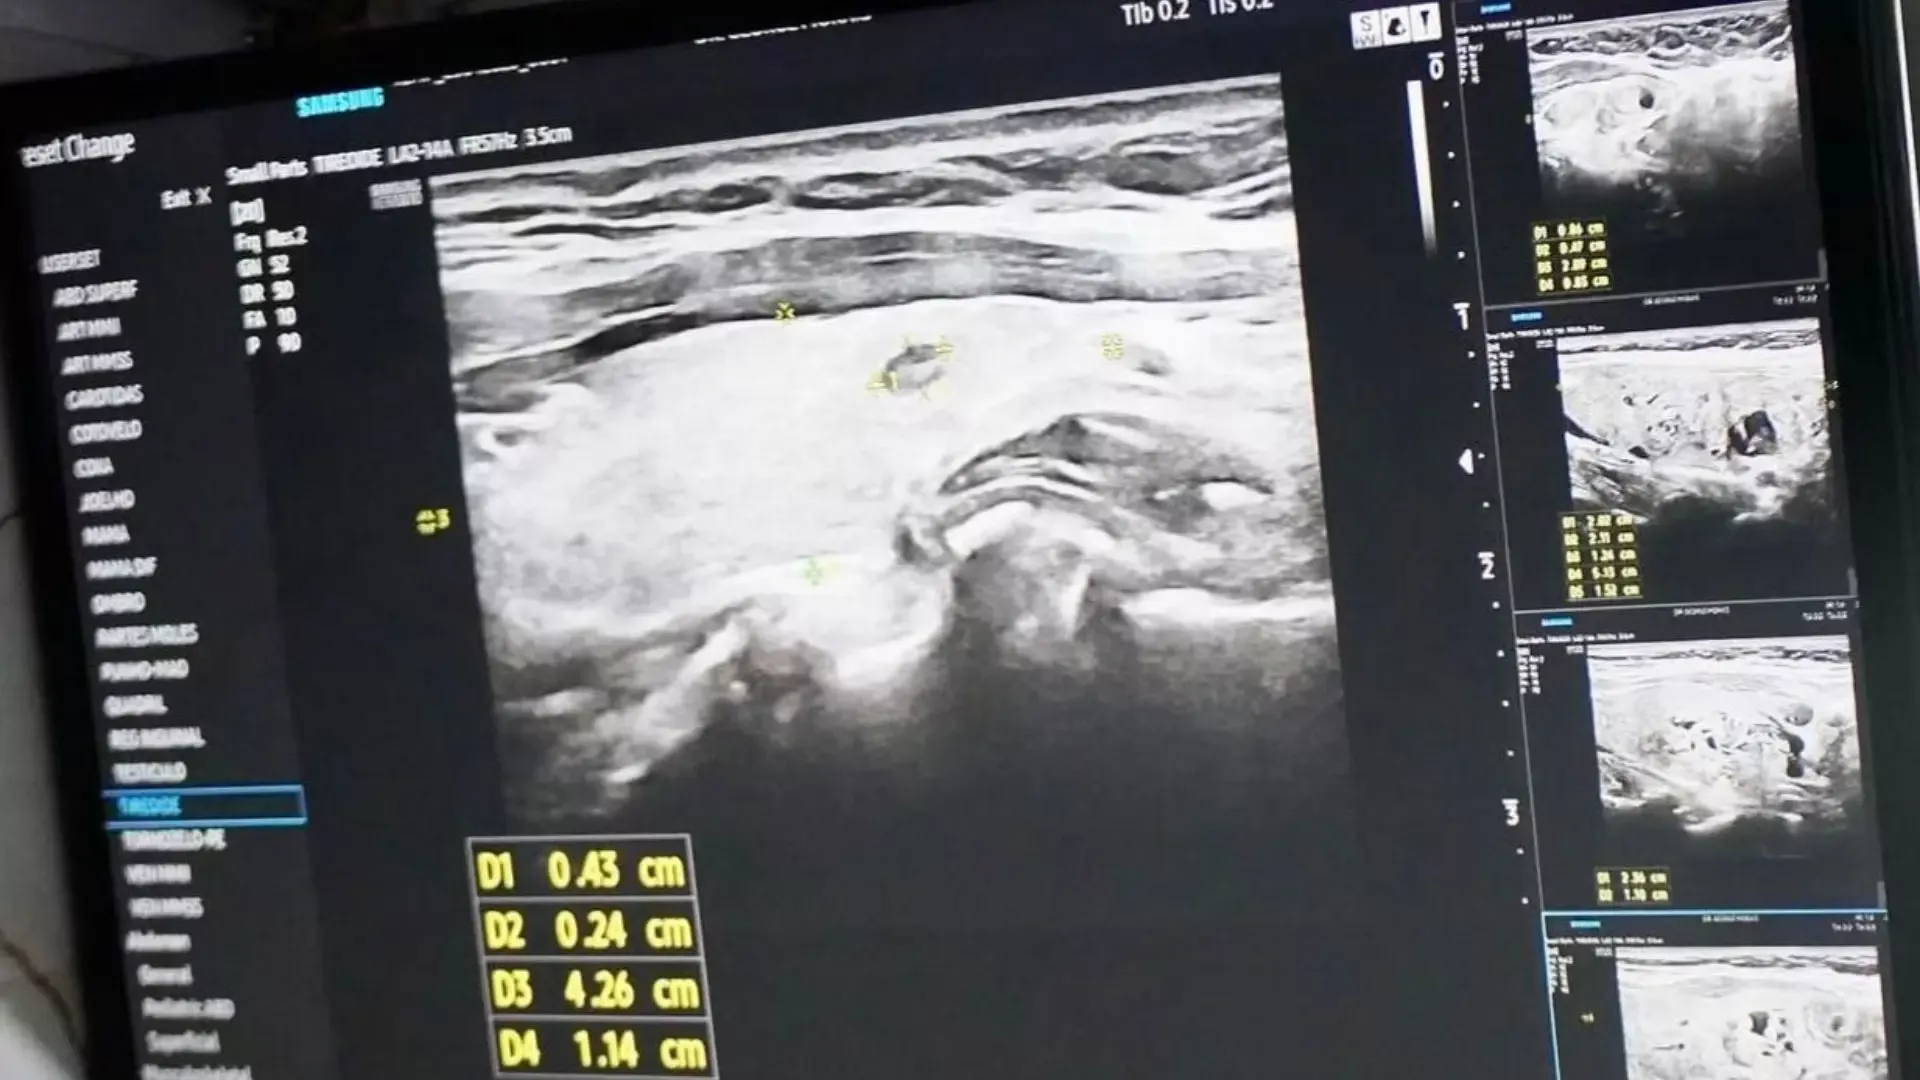

O ônibus da saúde foi a estrutura central do mutirão. Estacionado em ponto estratégico da cidade, o veículo recebeu cerca de 300 pessoas ao longo do dia. Médicos e técnicos realizaram ultrassonografias, avaliações clínicas e encaminhamentos para a rede pública.

Pacientes com alterações detectadas saíram com orientações e agendamentos para acompanhamento especializado, reduzindo o tempo de espera por diagnóstico.

A iniciativa reforça a importância do rastreio precoce da doença, que muitas vezes é silenciosa. Segundo especialistas que participaram da ação, identificar nódulos e alterações hormonais ainda em estágio inicial aumenta de forma significativa as chances de tratamento eficaz. A equipe também distribuiu material informativo e tirou dúvidas da população sobre sintomas, fatores de risco e prevenção.